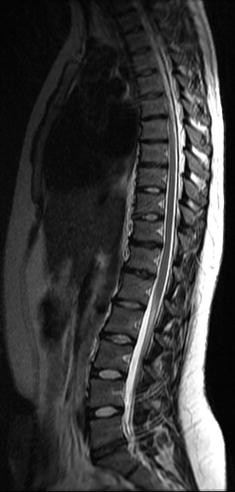

T11-t12 degenerative disc disease- Above Sagittal (side view) lumbar MRI shows lumbar disc degeneration of the bottom 3 discs Note the darkened color and loss of disc height suggesting disc desiccationThe gradual deterioration of the T1 to T12 facet joints, discs and vertebrae is often a byproduct of the natural aging process, but can also be attributed to overuse, poor body mechanics, traumatic